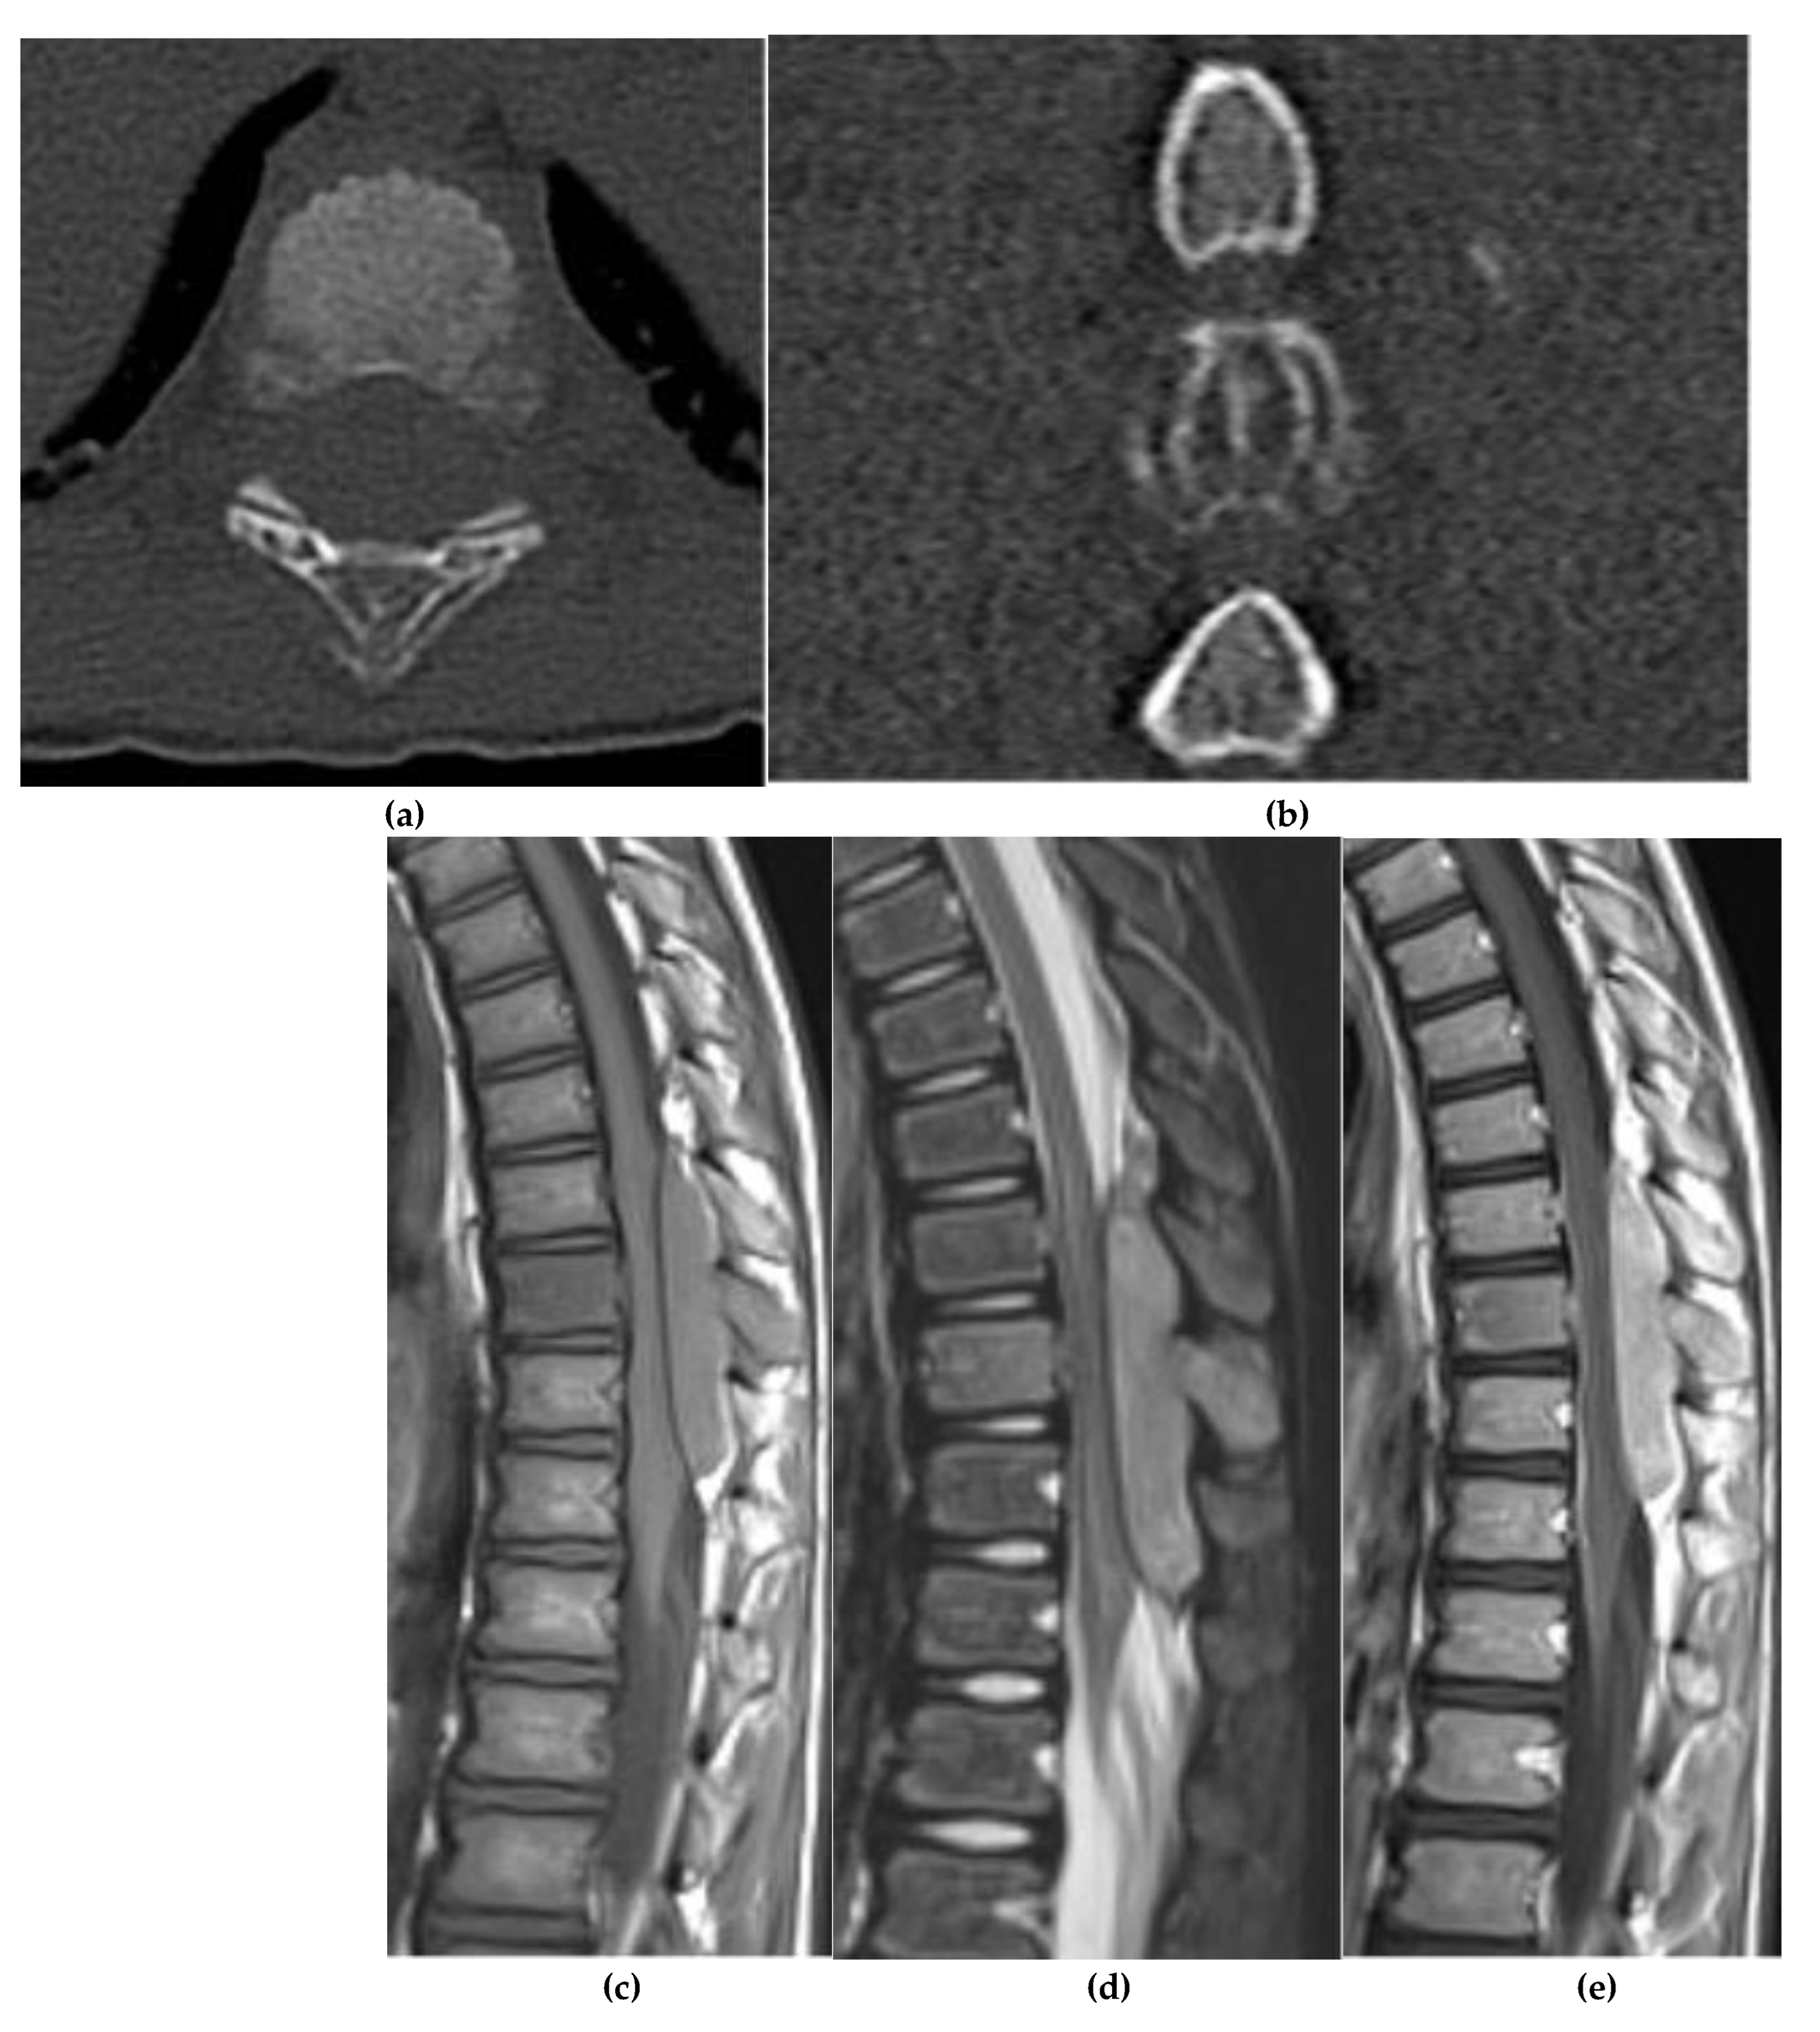

Aneurysmal Bone Cyst